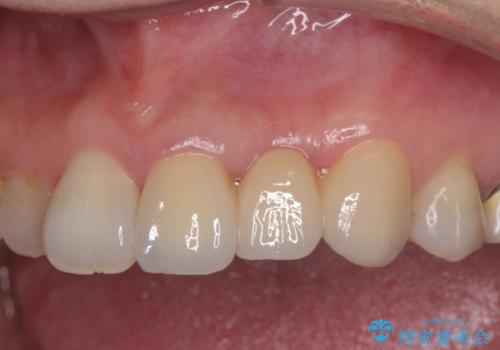

- 39.6万円(ジルコニアクラウン×3・仮歯×3)費用は治療当時の料金となります

精度、周囲の歯の色調にこだわったオールセラミックブリッジを作製し、しっかりと機能・審美性を改善することができました。